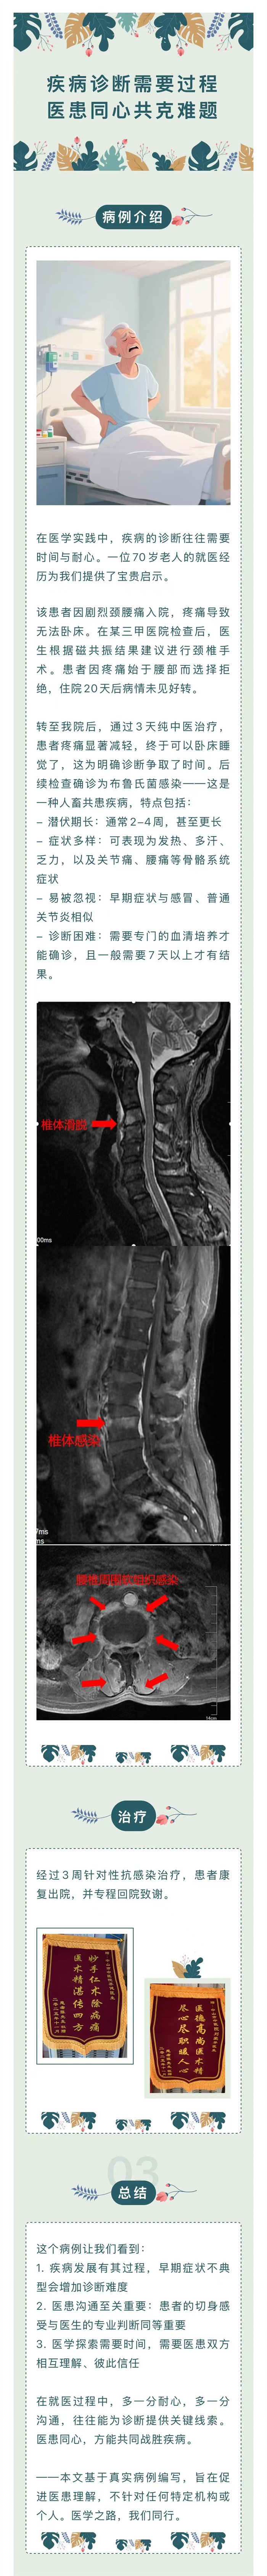

疾病诊断需要过程,医患同心共克难题